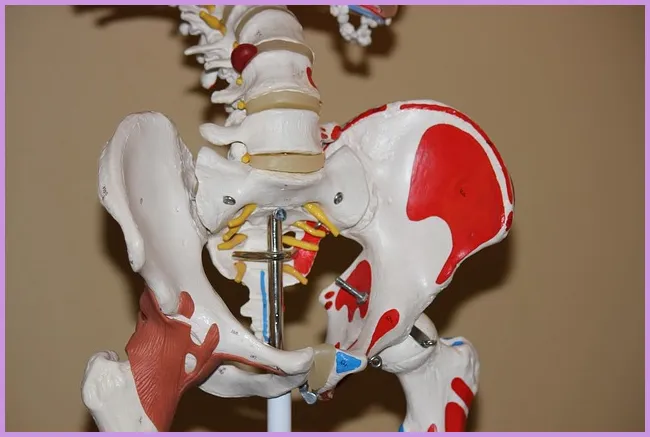

퇴행성 관절염의 예방 및 관리 전략

퇴행성 관절염을 예방하고 관리하기 위해서는 몇 가지 중요한 전략이 있습니다. 먼저, 규칙적인 운동이 필요합니다. 관절을 강하게 해주는 근육을 기르는 것이 중요하며, 수영이나 자전거 타기와 같은 저충격 운동이 좋습니다. 둘째로, 체중 조절이 중요합니다. 비만은 관절에 추가적인 부담을 주기 때문에, 건강한 식단과 운동을 병행하는 것이 필요합니다. 최근 연구에 따르면 건강한 체중을 유지하면 관절염의 증상을 완화하는 데 성공적이라고 합니다.